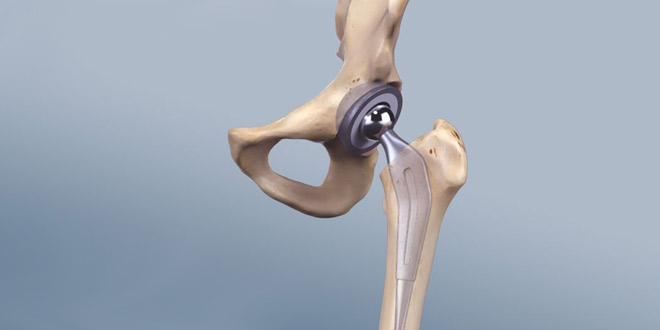

في جراحة استبدال مفصل الورك ، يتم استبدال مفصل الحوض (الورك) بمفصل اصطناعي ، وهو ما يسمى بدلة. يتكون مفصل الحوض من جزأين رئيسيين ؛ يمكن استبدال كلا الجزأين أثناء الجراحة بواسطة جراح الحوض. يتضمن هذان الجزءان تجويف الحوض ، وهو جزء من الحوض يسمى الحُق والنهاية العلوية للحوض أو رأس الحوض.